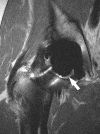

Background: Little is known about intraarticular pathology following THA prior to the radiographic appearance of osteolysis, primarily due to imaging limitations. MRI has recently been applied to imaging the postarthroplasty hip with the ability to detect periarticular bony and soft tissue pathology; specifically, it is able to detect abnormal synovial patterns and focal bone loss well before the radiographic appearance of osteolysis.

Methods: We recruited 31 patients (33 hips) who underwent routine noncemented THA with one of three types of bearing surfaces: metal-on-cross-linked polyethylene (n = 7), ceramic-on-ceramic (n = 12), and ceramic-on-cross-linked polyethylene (n = 14). Patients underwent specialized MRI at a minimum of 12 months (mean, 23 months; range, 12-37 months) after surgery. MR images were analyzed for the presence of synovitis or osteolysis. WOMAC scores, patient assessment questionnaires, and radiographic wear measurements were correlated with MRI findings.

Results: Reactive synovitis was observed in 13 of 33 patients (39%) and focal osteolysis in one of 33 (3%). The presence of synovitis did not correlate with pain, activity level, patient satisfaction or clinical outcome scales, nor did it correlate with radiographic wear measurements at early followup.